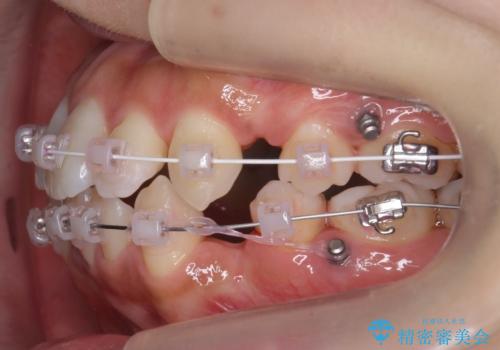

右上の半分埋まっている犬歯を抜歯し、残り上下左右3本抜歯してワイヤー矯正を行いました。

前歯が斜めになっているのもだいぶ改善しました。

犬歯の抜歯後は骨が少ない状態なのでブラックトライアングルは出てしまいましたが事前に説明をしております。